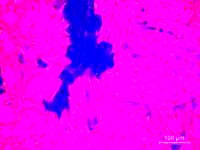

Ziel des Gesamtprojektes ist die grundlegende Erforschung und Entwicklung von zellbasierten Organstrukturen und einer darauf aufbauenden kompletten Regeneration geschädigter Organe, z.B. von Knochen mit integrierten Gefäßen. Basierend auf der Kombination von neuen Herstellungsverfahren für dreidimensionale Gerüststrukturen mit bioaktiven Materialien, spezifischen Wachstumsfaktoren und patienteneigenen Zellen soll die mikroanatomische Struktur von Knochen und Blutgefäßen nachgebildet werden. So sollen in Zukunft neue intelligente Therapien durch den Einsatz von maßgeschneiderten Biomaterialien sowie die Herstellung von kompletten Organen bzw. Organbestandteilen im Labor oder direkt im OP am bzw. im Patienten möglich werden. Durch diese Kombination wird die komplizierte und langwierige Kultivierung der Organe entfallen.